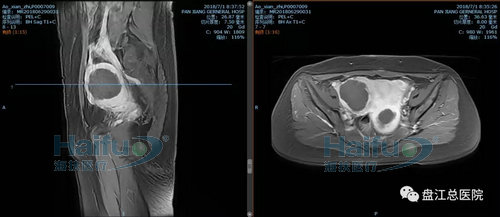

我院病例2:患者王XX,46歲,子宮腺肌癥患者。

因“發現盆腔包塊10+年,繼發性痛經2+年”入院。于2018年6月28日行高強度聚焦超聲消融治療(HIFU)。

治療經過:給予鎮靜鎮痛藥物后開始輻,患者訴稍有骶尾部及治療區脹痛不適,余未訴有不適,安靜休息配合治療。總治療時間25min。

術前磁共振增強橫斷位及矢狀位,見病灶內明顯強化

術后磁共振增強,見病灶內無明顯強化,病灶發生凝固性壞死